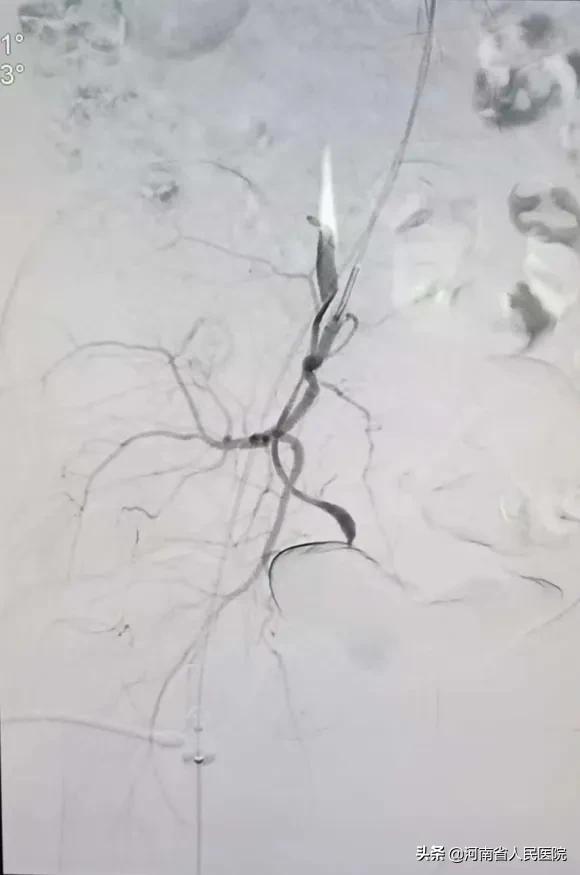

谁知一做血管造影才发现:患者两侧子宫动脉均不同于一般人,一侧是由 卵巢动脉 (锯齿状血管)“长途奔袭”去供应子宫血液,一侧是从 阴部内动脉 发出。

两个血管发出角度都很 刁钻 ,血管走形迂曲又比较细。

做这样的血管介入类似于医学版 “爬雪山过草地” ,大家不禁倒吸一口冷气!

栓塞后子宫的供血动脉不再显影